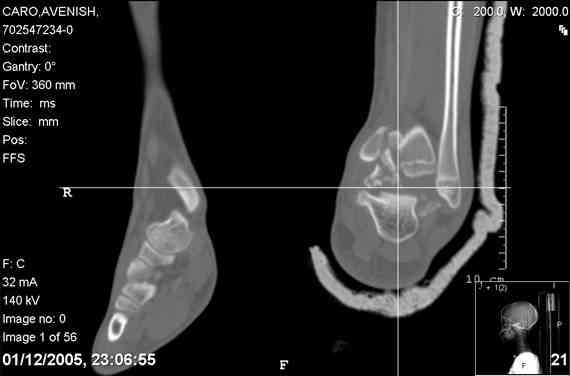

ya by popytalsya sobrat talus anatomichno,seichas pozdno operirovat

iz za oteka,po etomy distrakziya apparatom budet optmalna.Posyalu vam

podobyai moi sluchai.